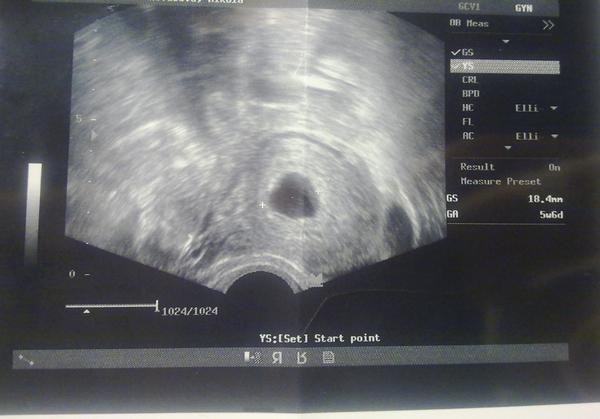

Som v 8tt od poslednej menštruácie. Sóno vypočítalo plod starý 6 +0 tt.

Na sóne nie je vidieť plod iba gestačný vačok, ktorý stále rastie má 19mm a žĺtkový vak 2mm.

Ďakujem Vám všetkým veľmi pekne za odpovede. Mne nie je vidno vôbec plod. Iba gestačný a žĺtkový vak. Preto neviem či sa oplatí ešte čakať na niečo. Ešte mám aj ten gestačný vačok nepravideľného tvaru. V pondelok by som mala byť 8+5tt od poslednej menštruácie.

Povedal, že podľa ultrazvuku vyzerá moje tehotenstvo na 6 týždeň a nie na 8. Najprv môj gynekológ a potom som bola ešte pre istotu v nemocnici u ďalšieho a to isté.

@doory problém nie je v srdiečku ☹ ale v tom , že mne tam nevidno stále vôbec plod gestačný vačok je prázdny. ☹ ☹ ☹